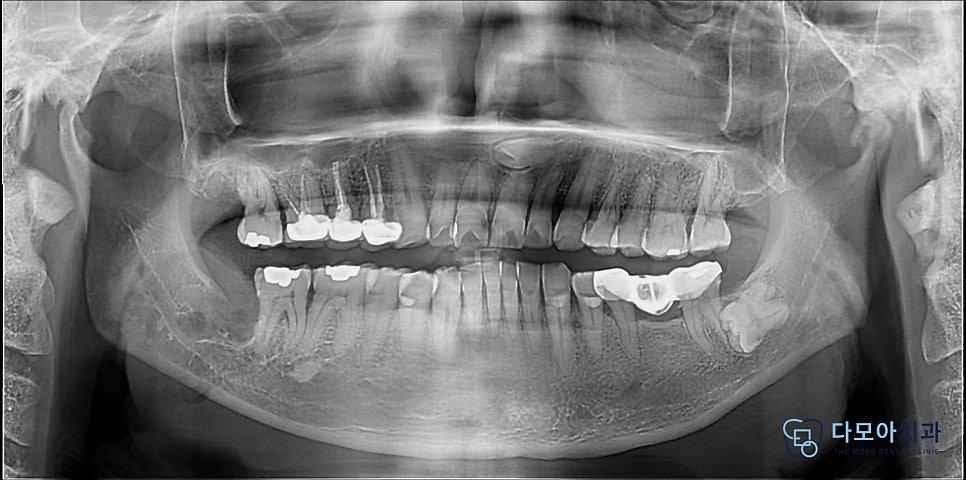

사랑니 발치 후 엑스레이 사진입니다.

확인해보니, 치근이 하치조신경에 닿아 있었으며

이 케이스는 난이도가 상당한 사랑니 발치 케이스였지만,

당일 발치를 진행하기로 했습니다.

발치 시 하치조신경을 잘못 건드리면

감각 이상 등 후유증이 발생할 수 있기 때문에

이 부분을 고려하여 조심조심 발치를 진행했답니다.